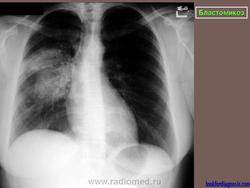

Рентгенологически отмечаются выраженные изменения лимфатических узлов средостения, очаговые инфильтраты, в некоторых из них развиваются каверны с неправильными контурами. При диссеминации процесс захватывает многие органы, эти формы часто заканчиваются гибелью больного.